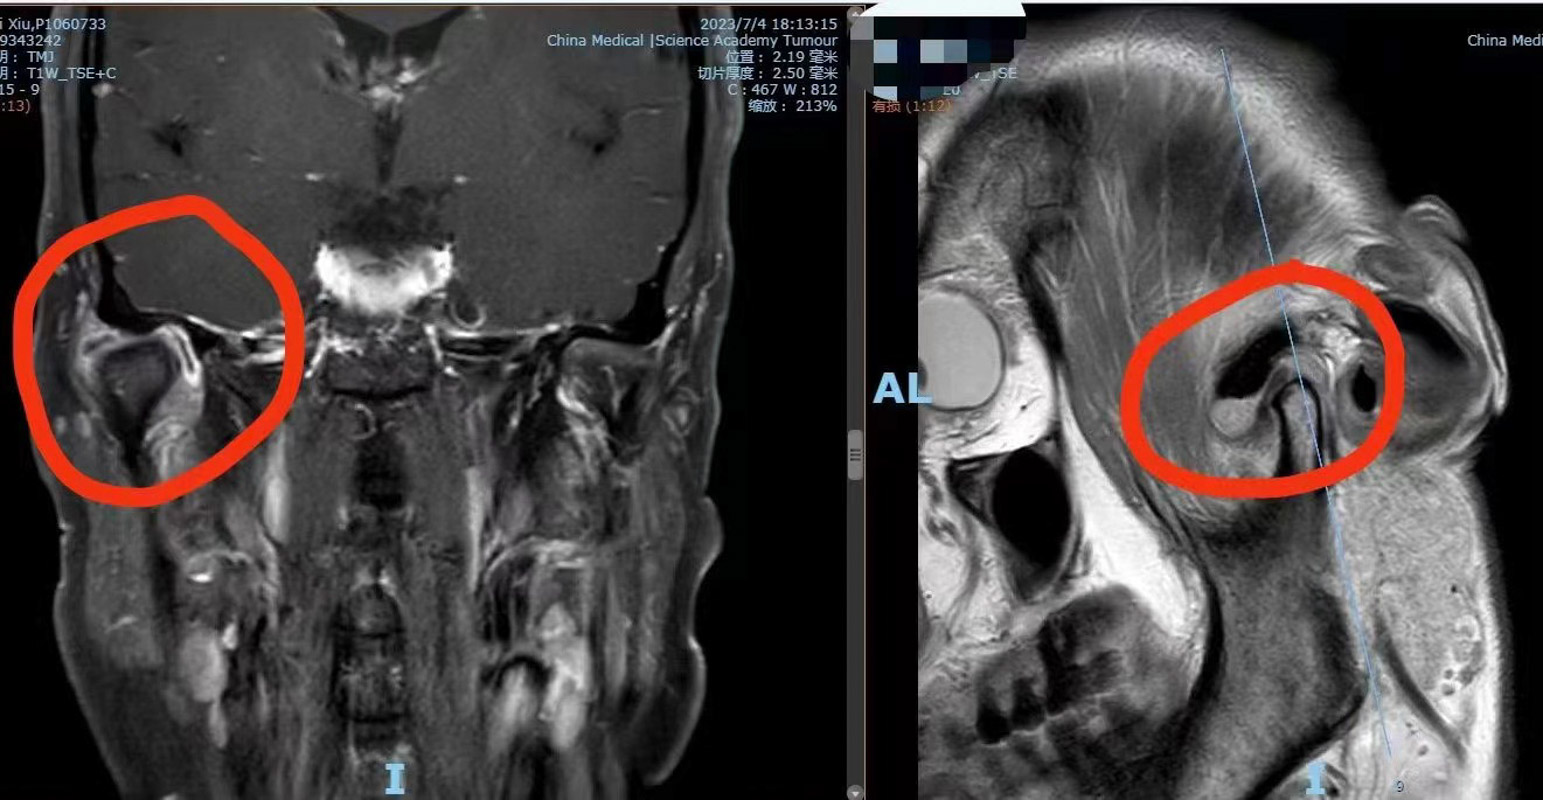

口腔科副主任醫師劉彥杰了解患者情況后,馬上安排患者進行顳下頜關節磁共振檢查,結果顯示其右邊顳下頜關節囊擴張,內里有局部鈣化樣病變。“有可能是顳下關節滑膜軟骨瘤,這種疾病在顳下頜關節處十分罕見。”醫生根據患者情況結合多年的臨床經驗解釋道。

滑膜軟骨瘤是一種在膝關節比較常見,顳下頜關節十分罕見的疾病。原發性滑膜骨軟骨瘤病(SynovialChondromatosis)又稱滑膜軟骨化生(SynovialChondrometaplasia),是一種良性關節病,由滑膜軟骨化生而引起,以滑膜上形成軟骨結節為特征。這些軟骨小體多呈砂粒狀,多時可達數十個,可帶蒂生長,向關節腔內突出,亦可脫落進入關節腔內,成為游離體(關節鼠),受關節滑液滋養而逐漸長大,后期軟骨結節可發生鈣化或骨化,如“小石頭”一般,所以也稱滑膜骨軟骨瘤病。